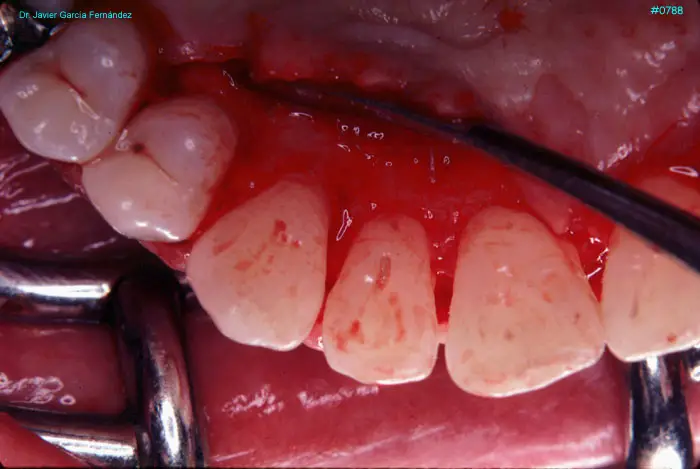

Atlas of Surgical Techniques in Periodontics. Chapter III. Atlas de Técnicas Quirúrgicas en Periodoncia